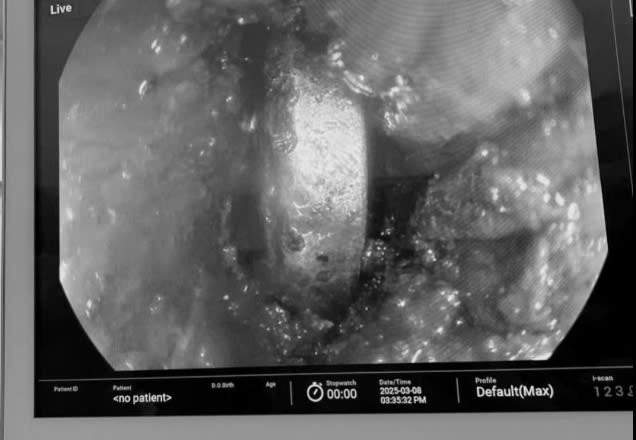

| Gắp dị vật pin cúc áo trong thực quản bệnh nhi. Ảnh BVCC |

Các nỗ lực gắp pin ra đều khó khăn, ê-kíp đã sử dụng ống mềm nội soi, ống cứng nội soi một lỗ để gắp ra nhưng đều bị kẹt lại do hẹp đầu ra.

Sau 3 giờ nỗ lực, ê-kíp cùng bác sĩ Quách Văn Nam (khoa Tiêu hoá) đã thành công lấy được dị vật mà không cần can thiệp phẫu thuật mở, giúp bé tránh khỏi nguy cơ thủng thực quản và hồi phục tốt hơn sau can thiệp.